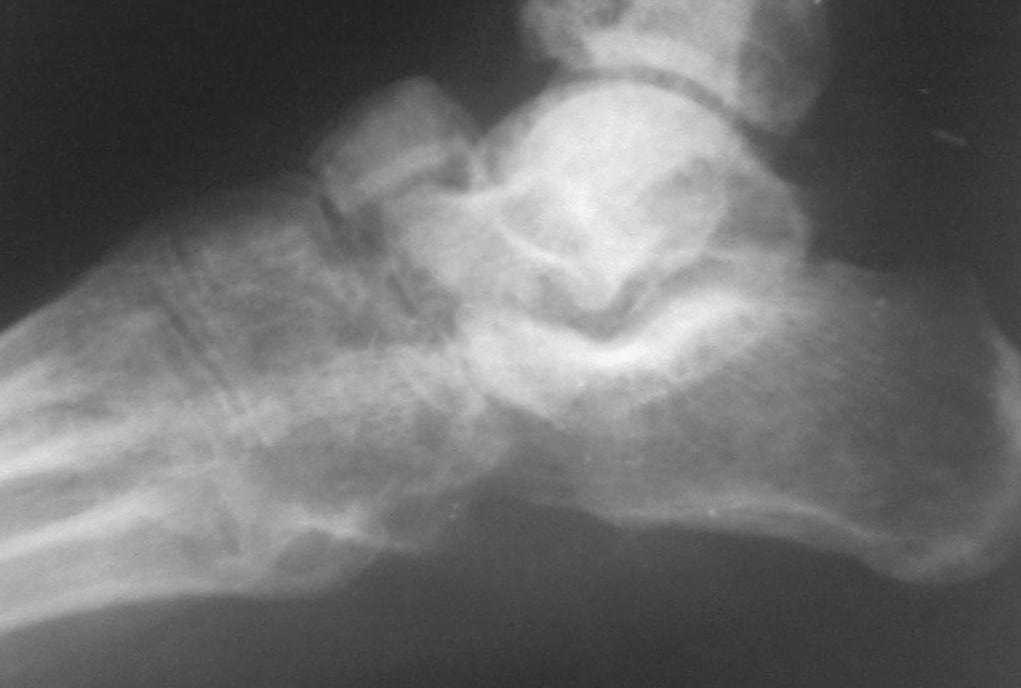

[Ortho] Застарелый вывых ладьевидной кости стопы

По  данному  случаю,  оказалось  3  месяца  назад  было  произведена Р-графия в  райбольнице,  но  больной предпочел  лечится  у  табиба. Присылаю  первичные  снимки.

Имя     : SP_A0177.jpg

Url     : http://weborto.net:8080/pipermail/ortho/attachments/20080406/e30b47f8/attachment-0003.jpg